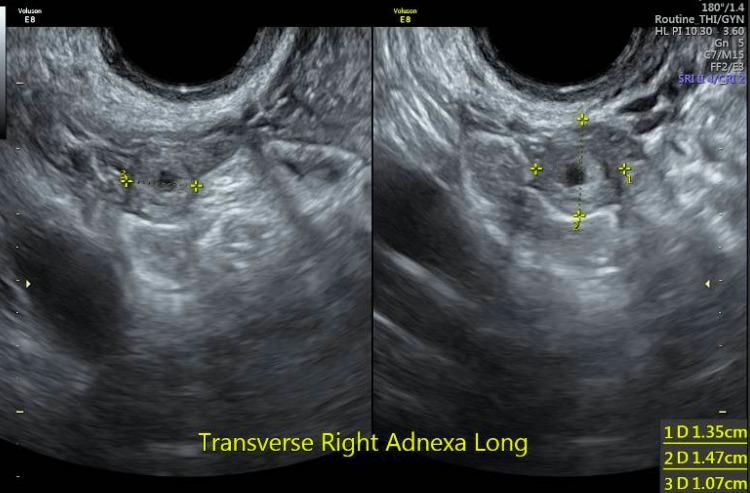

Spontaneous bilateral ectopic pregnancies are rare. In the majority of case reports, treatments prescribed were methotrexate, bilateral salpingectomy, or salpingectomy/salpingostomy. A 31-year-old gravida 3 para 0 at our institution underwent diagnostic laparoscopy due to ruptured ectopic pregnancy, and based on visual inspection, had a bilateral ectopic pregnancy. She underwent right salpingectomy for a ruptured ectopic pregnancy and had spontaneous expulsion of the left ectopic pregnancy with mobilization of the fallopian tube. She received methotrexate as per the two-dose protocol and was followed with a negative beta-human chorionic gonadotropin (b-hCG). Pathology confirmed bilateral tubal ectopic pregnancies. Spontaneous bilateral tubal ectopic pregnancy requires a high level of clinical suspicion. If a tubal pregnancy has expulsion of tissue intraoperatively, a two-dose protocol for methotrexate administration may be used for treatment, especially in the case of a bilateral ectopic pregnancy with fertility desires.

自发性双侧异位妊娠较为罕见。在大多数病例报告中,所采用的治疗方法为甲氨蝶呤、双侧输卵管切除术或输卵管切除术/输卵管造口术。我院一名31岁、孕3产0的患者因异位妊娠破裂接受了诊断性腹腔镜检查,经肉眼观察发现为双侧异位妊娠。她因右侧异位妊娠破裂接受了右侧输卵管切除术,左侧异位妊娠随输卵管活动自行排出。她按照两剂方案接受了甲氨蝶呤治疗,随后β-人绒毛膜促性腺激素(β-hCG)检测结果为阴性。病理检查证实为双侧输卵管异位妊娠。自发性双侧输卵管异位妊娠需要高度的临床怀疑。如果术中发现输卵管妊娠有组织排出,可采用两剂甲氨蝶呤给药方案进行治疗,尤其是对于有生育意愿的双侧异位妊娠患者。